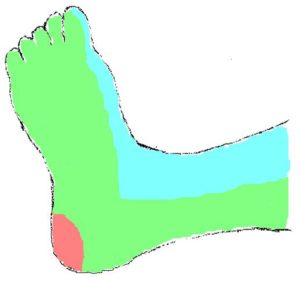

The foot consists of 6 angiosomes in total (Figure 1):

- The posterior tibial supplies 3 angiosomes through the medial calcaneal, medial plantar, and lateral plantar braches (medial ankle and plantar surface).

- The anterior tibial artery supplies the dosalis pedis angiosome encompassing the entire dorsal aspect of the foot.

- The peroneal artery supplies 2 angiosomes through the lateral calcaneal and anterior perforating branches (lateral heel and anterolateral ankle).

Sometimes, the severity and distribution of the infra-popliteal disease prevent an angiosome-guided revascularization strategy. For example, in a patient with a medial heel ulcer, angiography may reveal proximal occlusions of the peroneal and posterior tibial arteries, and a severely diseased anterior tibial artery that is supplying the only perfusion to the foot (Figure 1). Revascularizing the anterior tibial artry is technically most feasible, though this in essence ignores the angiosome principle which would require recanalizing a lengthy chronic occlusion of the posterior tibial artery. Thus, angiosome-guided revascularization is not uniformly achievable in all patients, particularly in those receiving endovascular techniques.